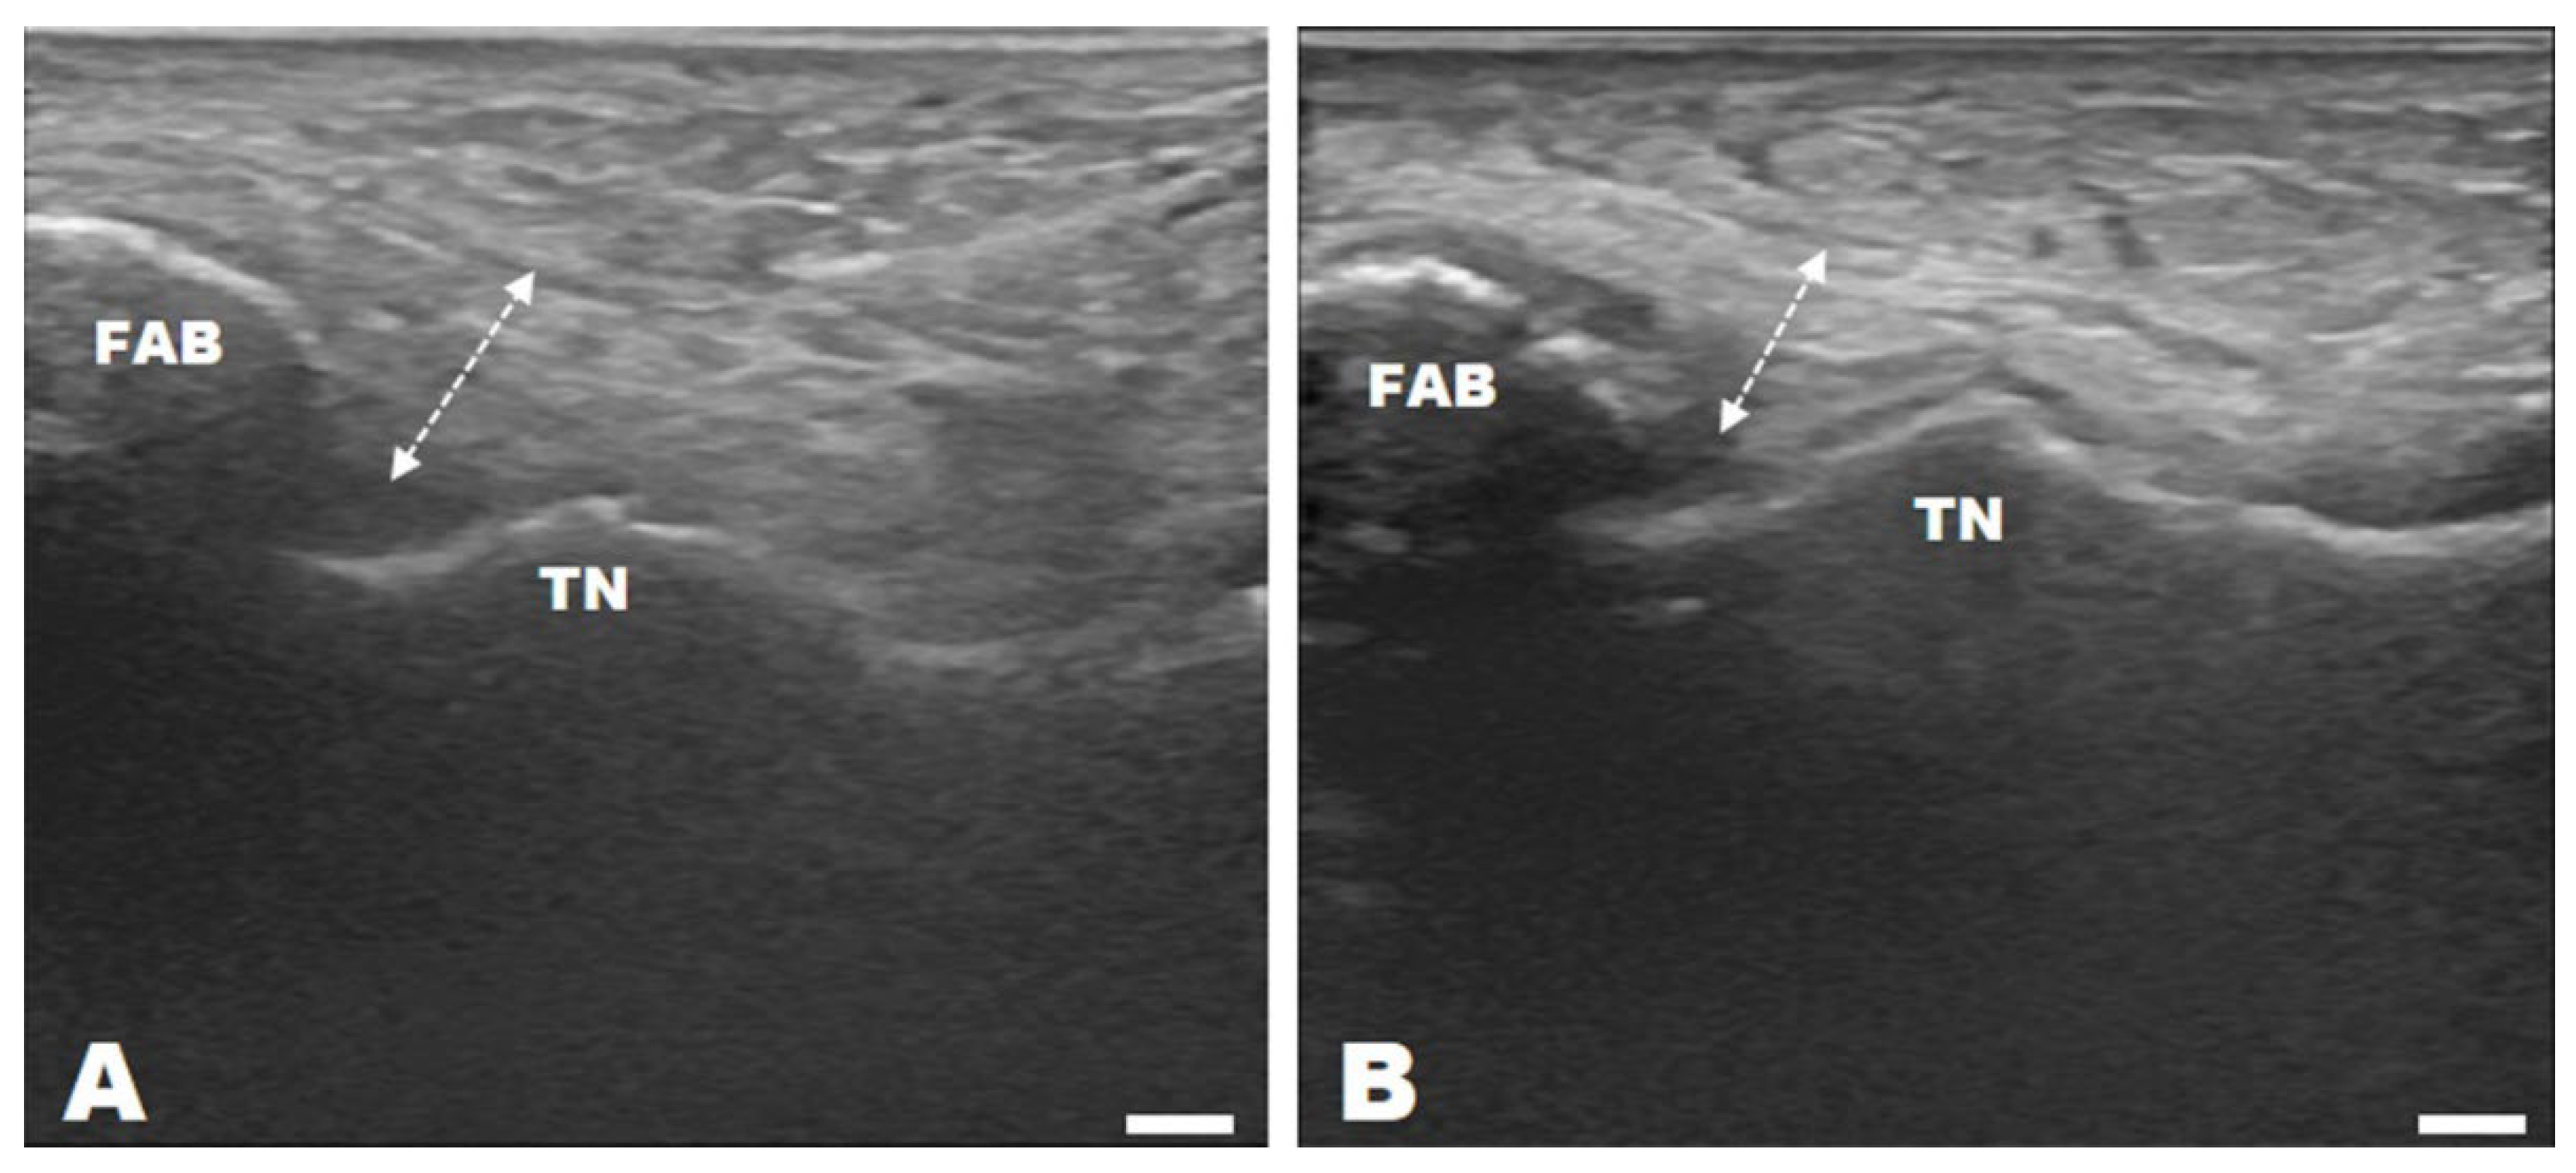

2.6. Ultrasonography